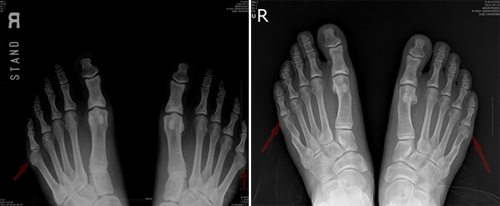

소건막류 환자의 수술 전(왼쪽), 수술 후(오른쪽) 사진(사진=연세견우정형외과 제공)

소건막류는 새끼발가락이 바깥쪽으로 튀어나오는 질병이다. 새끼발가락 뼈가 휘어서 돌출되거나 뼈 자체의 변형이 생기기도 하고, 네 번째 발가락과 새끼발가락이 벌어져서 나타나기도 한다. 선천적으로 새끼발가락에 이상이 있어서 생기는 경우도 있지만, 자신의 발 폭보다 좁은 신발을 오랫동안 신었을 때 발병한다. 앞 코가 좁은 신발은 새끼발가락에 과한 마찰과 압력을 준다. 계속해서 압력을 받으면 새끼발가락이 바깥쪽으로 튀어나오고 빨갛게 변한다.

소견막류를 예방하기 위해서는 신발을 고를 때는 앞이 뾰족한 신발보다는 발 폭 위주로 골라서 발가락과 신발의 마찰을 줄이는 것이 좋다. 소건막류가 초기 증상일 때는 큰 신발이나 깔창을 신는 치료를 하지만 효과가 없을 때는 수술치료를 해야 완치가 가능하다. 연세견우정형외과 박의현 원장은 "최근에는 돌출된 뼈를 제거하지 않고 새끼발가락을 네번째발가락과 평행하게 안으로 밀어넣는 수술로 완치가 가능하다"며 "발목마취를 하고 수술시간도 10분 정도가 소요돼 빠른 일상생활 복귀가 가능하다"고 말했다.